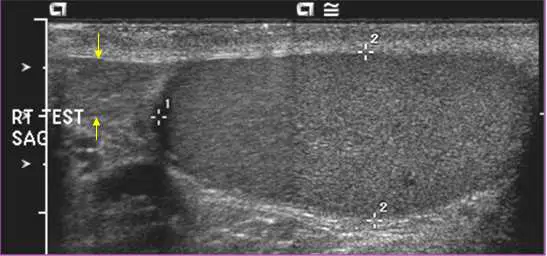

本題影像標記為「RT TEST SAG」,即右側睪丸縱切面掃描(right testis sagittal view)。

影像右側可見一顆大型、橢圓形、均勻中等回音(homogeneous intermediate echogenicity)的結構,此為睪丸(testis),其內部回音均勻,周圍有薄層強回音之白膜(tunica albuginea)包覆。測量游標(+)標示於睪丸的上下極。

黃色箭號指向睪丸左上方(上極後方)一個略呈月牙形、回音略高於或等同於睪丸的小結構,其位於睪丸後外側緊鄰處,形態為逗點狀——這正是**副睪丸(epididymis)**的頭部(caput epididymis)典型外觀。正常副睪頭回音為等回音至稍強回音(isoechoic to slightly hyperechoic),尺寸約 10–12 mm,恰與影像所示相符。

影像中並無明顯腫塊、積液或不均勻回音,整體為正常陰囊超音波表現。